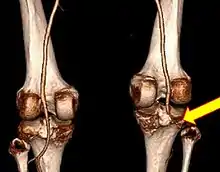

| Plain lateral X-ray of the left knee showing a posterior knee dislocation[1] | |